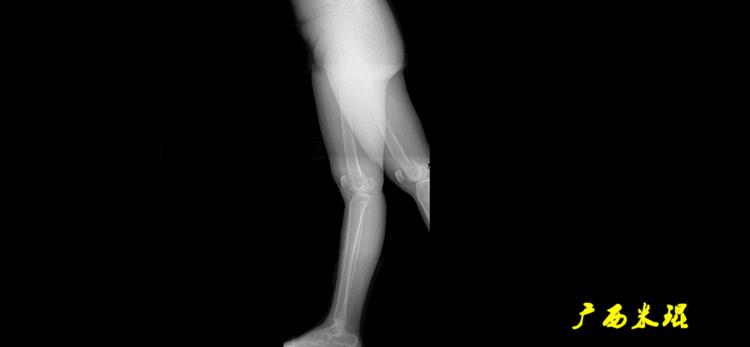

站立侧位(矢状面)股骨头中心与踝关节中心的连线也通过膝关节中心,这也是下肢的机械轴线,这也是下肢力线。

矢状面的下肢力线常常被医生忽视,其实它的改变也是膝关节疼痛的常见原因。

胫骨近端后倾角(PPTA):胫骨平台关节面有平均10°的后倾,其中内侧后倾约12°,外侧后倾约7°。矢状面上胫骨平台的切线与胫骨解剖轴形成的夹角叫胫骨近端后倾角,正常为80°±3°。

胫骨远端前倾角(ADTA):矢状面上胫骨远端的关节切线与胫骨解剖轴形成的夹角叫胫骨远端前倾角,正常为80°±2°。